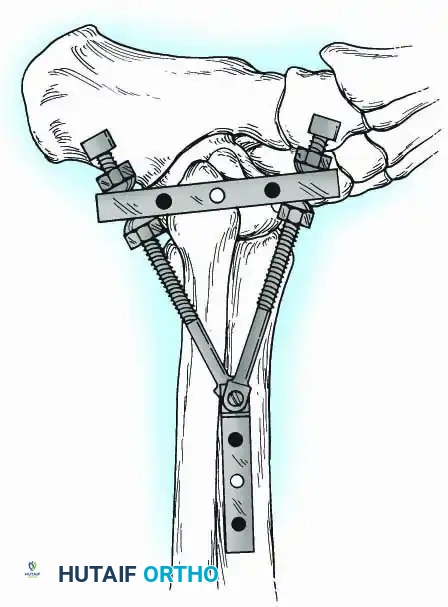

External Fixation

Historically pioneered by Charnley, external compression arthrodesis utilizes pins placed through the distal tibia and the body of the talus. Because Charnley's original uniplanar device lacked rotatory stability, Calandruccio designed a triangular frame to control motion in all three planes while applying massive compression.

Modern iterations, such as the Calandruccio II compression device, offer greater latitude in pin placement to avoid compromised skin. Ring or circular external fixators (Ilizarov, Taylor Spatial Frame) are the gold standard for salvage situations, including active infection, massive bone loss, or failed TAA, as they allow for simultaneous compression, deformity correction, and early weight-bearing.

Knee Arthrodesis

While total knee arthroplasty (TKA) is the definitive treatment for knee osteoarthritis, knee arthrodesis remains a critical salvage procedure. The primary indications are a chronically infected TKA that has failed two-stage revision, massive extensor mechanism disruption, severe neuropathic arthropathy, and tumor resection.

Positioning and Technique

The optimal position for knee arthrodesis is 10 to 15 degrees of flexion and 5 to 7 degrees of valgus. This slight flexion assists in foot clearance during the swing phase of gait and makes sitting in confined spaces more manageable. A perfectly straight (0 degrees) knee is cosmetically awkward and functionally detrimental, causing a vaulting gait pattern.